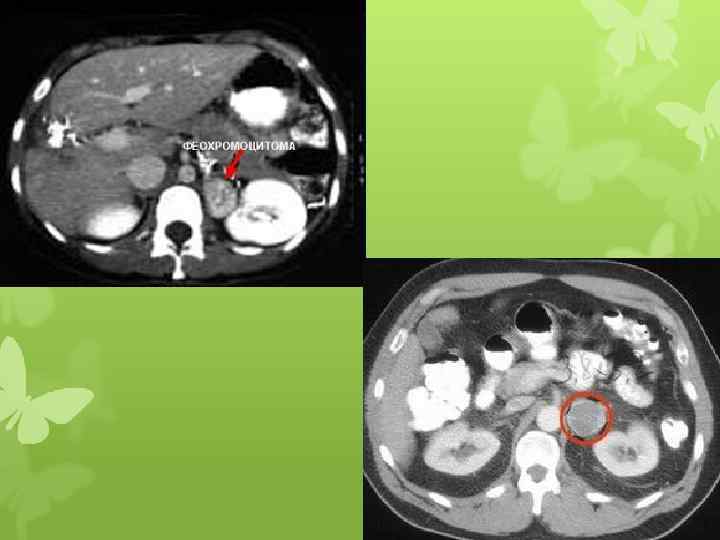

Феохромоцитома левого надпочечника Осл. : Вторичная артериальная гипертензия, стабильная форма

Феохромоцитома Болезнь, синдром Иценко-Кушинга Гормонально-активная опухоль, развивается из хроматоффинных клеток, расположенных в мозговом веществе надпочечников, реже – из экстраадреналовой хромаффинной ткани. Заболевание, обусловленное опухолью гипофиза или гиперплазией аденоматозных клеток. Синдром, когда гиперкортицизм обусловлен развитием опухоли коры надпочечников или двусторонней гиперплазией коры надпочечников. ↑ количества катехоламинов (преимущественно норадреналина) -> гиперкинетический тип кровообращения, вазоконстрикция, ↑ ОПСС -> активация РААС, что способствует прогрессированию АГ. Повышение концентрации в моче и плазме крови - катехоламинов Болезнь ИК: наличие опухоли гипофиза или гиперплазия аденоматозных клеток -> ↑АКТГ -> ↑продукции гормонов коры надпочечников, с развитием клинической картины гиперкортицизма. Синдром ИК: опухоли коры надпочечников или двусторонней гиперплазией коры надпочечников -> гиперкортицизм. Повышение концентрации в моче и плазме крови – глюкокортикоидов Объемное образование в области надпочечника, выявляемое при КТ изменения по данным КТ черепа или увеличение обоих надпочечников